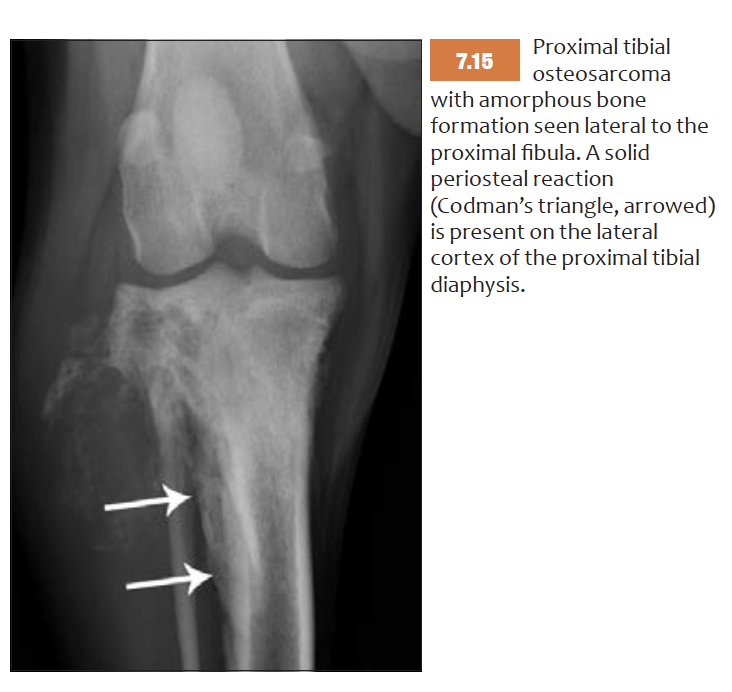

List features of amorphous bone production

NOT PERIOSTEAL REACTION -> neoplastic new bone, beyond confines of periosteum

=> cotton wool or candyfloss appearance

Highly suggestive of OSA